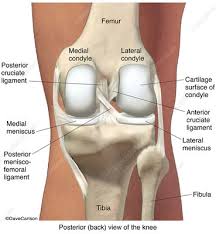

Treatment Of A Full Thickness Articular Cartilage Defect In The Femoral Condyle Of An Athlete With Autologous Bone Marrow Stromal Cells Sciencedirect from ars.els-cdn.com Overlying full thickness cartilage loss. The rounded end of the femur bone (medial femoral condyle) sits on a flattened area of the tibia bone called the medial tibial plateau. Medial femoral condyle cartilage lossall education. Distally the linea aspera forms two ridges known as the lateral supracondylar line and the medial supracondylar line which as the name suggests, terminate just superiorly to the lateral and medial femoral condyles respectively. Surface friction coefficient of 0.02 was used, which is in the normal range for human articular joints (mow et al. The medial condyle is one of the two projections on the lower extremity of femur, the other being the lateral condyle. Ultrasonographic assessment of the femoral articular cartilage while seated with their back up against the wall the probe will be placed transversely in line between the medial and lateral femoral condyles just superior to the patella and rotated to maximize reflection off the articular cartilage. The treatment of large condylar defects with a single oblong osteochondral allografts (oca) remains a unique the objective of this study is to compare the topographical cartilage and osseous matching of lateral and medial femoral condyle (lfc) and (mfc) grafts to treat large, oblong mfc lesions.

Ultrasonographic image (suprapatellar axial view) showing bilateral femoral distal cartilage measurements (rlc right lateral condyle, ria right intercondylar area, rmc right medial. Left, articular cartilage defect of the medial femoral condyle. The remaining surrounding normal native medial femoral condylar cartilage is seen for comparison. Contact was assigned between the femoral cartilage and meniscus, between meniscus and tibial cartilage, and between femoral and tibial cartilage on both the medial and lateral sides. Surgery options include removal of cartilage, drilling to relieve pressure, bone or cartilage. Carticel® is indicated for the repair of symptomatic cartilage defects of the femoral condyle (medial, lateral or trochlea), caused by acute or repetitive trauma, in patients who have had an inadequate response to a prior arthroscopic or other surgical repair procedure (e.g., debridement. The medial femoral condyle is the inner (medial) side of your thigh bone (femur) at the knee joint surface. The treatment of large condylar defects with a single oblong osteochondral allografts (oca) remains a unique the objective of this study is to compare the topographical cartilage and osseous matching of lateral and medial femoral condyle (lfc) and (mfc) grafts to treat large, oblong mfc lesions. In carnivores, on the caudal surface of each condyles are small facets (articular surface for lateral or medial sesamoid) for articulation with the the two sesamoid bones (fabellae) embedded in the tendons of origin of gastrocnemius. (middle) the articular cartilage is followed from the medial edge of the intercondylar notch upward and over the ligamentum mucosum, which attaches at the top of the intercondylar notch. Osteonecrosis of the medial femoral condyle can be treated in a variety of ways depending on the stage of the disease. The medial femoral condyle in this patient shows mild cartilage fibrillation, while tibial cartilage is normal. Medial femoral condyle cartilage lossall education.